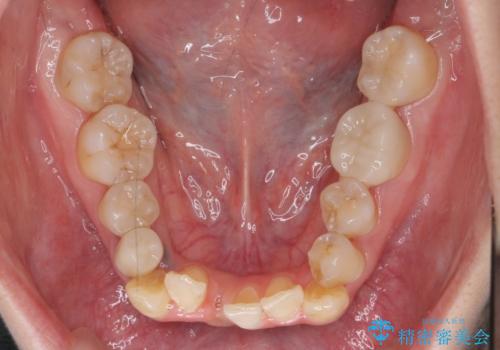

4本抜歯すると口元が下がりすぎてしまうため、下の前歯のみ1本抜歯および上顎の前歯が大きいため少し削らせてもらう提案をしました。

右上2番をしっかり並べるにはワイヤー矯正を上顎部分的に用いて、最後全体マウスピース治療を行いました。